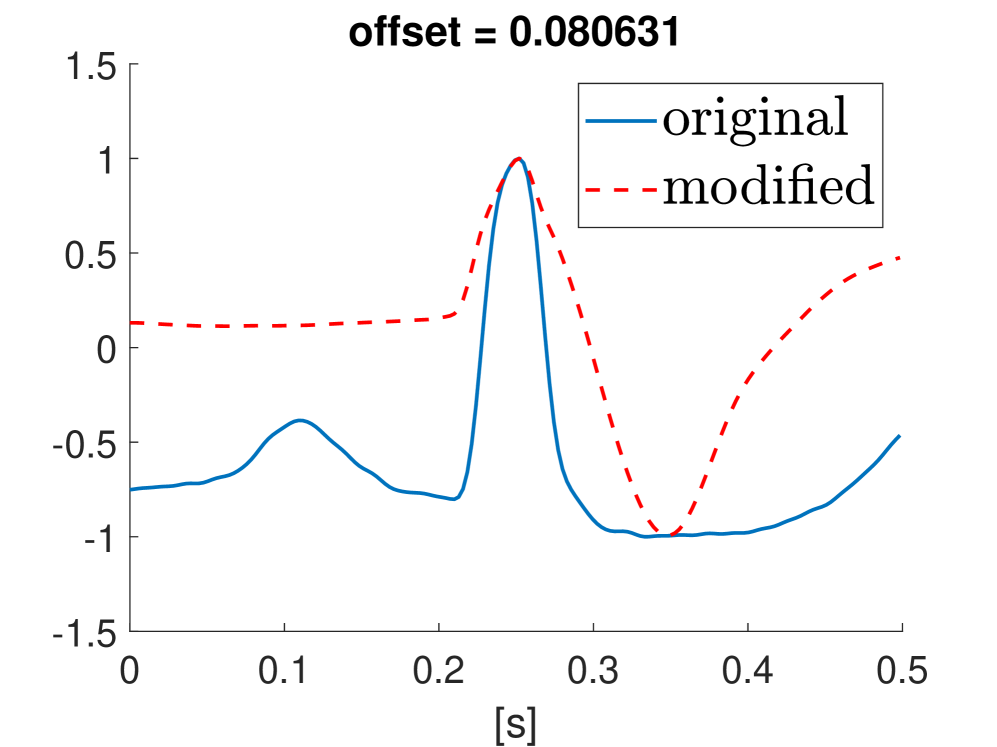

Fig. 10 shows the result in input space of moving along the first principal components in the latent feature space. As original base point we take a normal beat signal, i.e. corresponding to a hidden unit on the bottom right of Fig. 9(a). The smooth transition between the beat patterns allows for interpretation of the first principal components. This allows a clinical expert to understand on what basis the paced beats are separated by the principal components and if this basis has a physiological meaning. In order to investigate the separated region of the latent space at the top of Fig. 9(b) we start from a paced beat pattern and vary along the third principal component. This allows us to see which sort of heartbeat patterns are responsible for this specific distribution in the latent space.